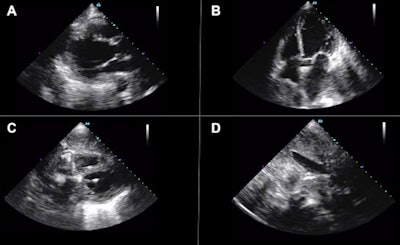

In one case, the AI-guided cardiac ultrasound exam showed a severe dilated and dysfunctional right ventricle, a hyperdynamic left ventricle, a mitral valve prosthesis, and a dilated inferior vena cava in a 65-year-old woman with a history of rheumatic heart disease and suspicion of COVID-19.

As a result, the patient's primary insult was determined to be progressive pulmonary hypertension with subsequent right ventricular failure. The patient, who remained negative for SARS-CoV-2, improved with heart failure management, according to the authors.

In another case, a 76-year-old woman with acute hypoxemic respiratory failure from acute left ventricular failure received a POCUS exam that demonstrated new severe left ventricular dysfunction.

Her SARS-CoV-2 test was negative, and the treating clinician changed the treatment strategy to a regimen for acute heart failure. The patient's condition worsened, however, and she died after a transition to comfort-focused care, according to the researchers.